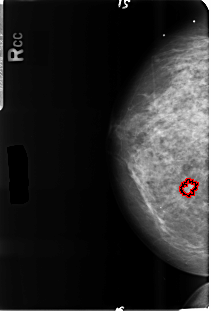

B_3500_1.RIGHT_CC

RIGHT_CC LINES 4656 PIXELS_PER_LINE 3160 BITS_PER_PIXEL 12 RESOLUTION 50 OVERLAY

FILE: B_3500_1.RIGHT_CC.OVERLAY

TOTAL_ABNORMALITIES 1

ABNORMALITY 1

LESION_TYPE CALCIFICATION TYPE ROUND_AND_REGULAR-PUNCTATE DISTRIBUTION DIFFUSELY_SCATTERED

ASSESSMENT 2

SUBTLETY 1

PATHOLOGY MALIGNANT

TOTAL_OUTLINES 1